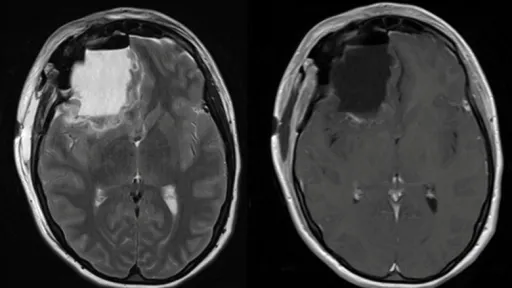

Peste 100 de persoane care au absolvit același liceu din New Jersey au fost diagnosticate cu forme rare de cancer cerebral, context în care a fost declanșată o investigație pentru a se stabili dacă există vreo legătură între ele.

Investigația demarată luna trecută a vizat contextul în care peste 100 de elevi care au mers la același liceu din New Jersey au făcut o formă rară de cancer cerebral. Ancheta nu a găsit nicio legătură între școală și diagnostic.

Luna trecută, Al Lupiano a spus că a fost diagnosticat cu această boală când avea 27 de ani. Ulterior, sora și soția lui au fost și ele diagnosticate cu cancer cerebral. Toți trei au urmat cursurile liceului Colonia din Woodbridge, New Jersey, scrie Insider.

NBC Today a raportat că peste 100 de elevi care au mers la acel liceu au avut același diagnostic.